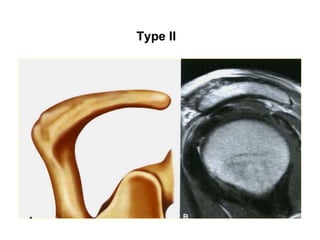

Type I

Type II

Type III

Type IV